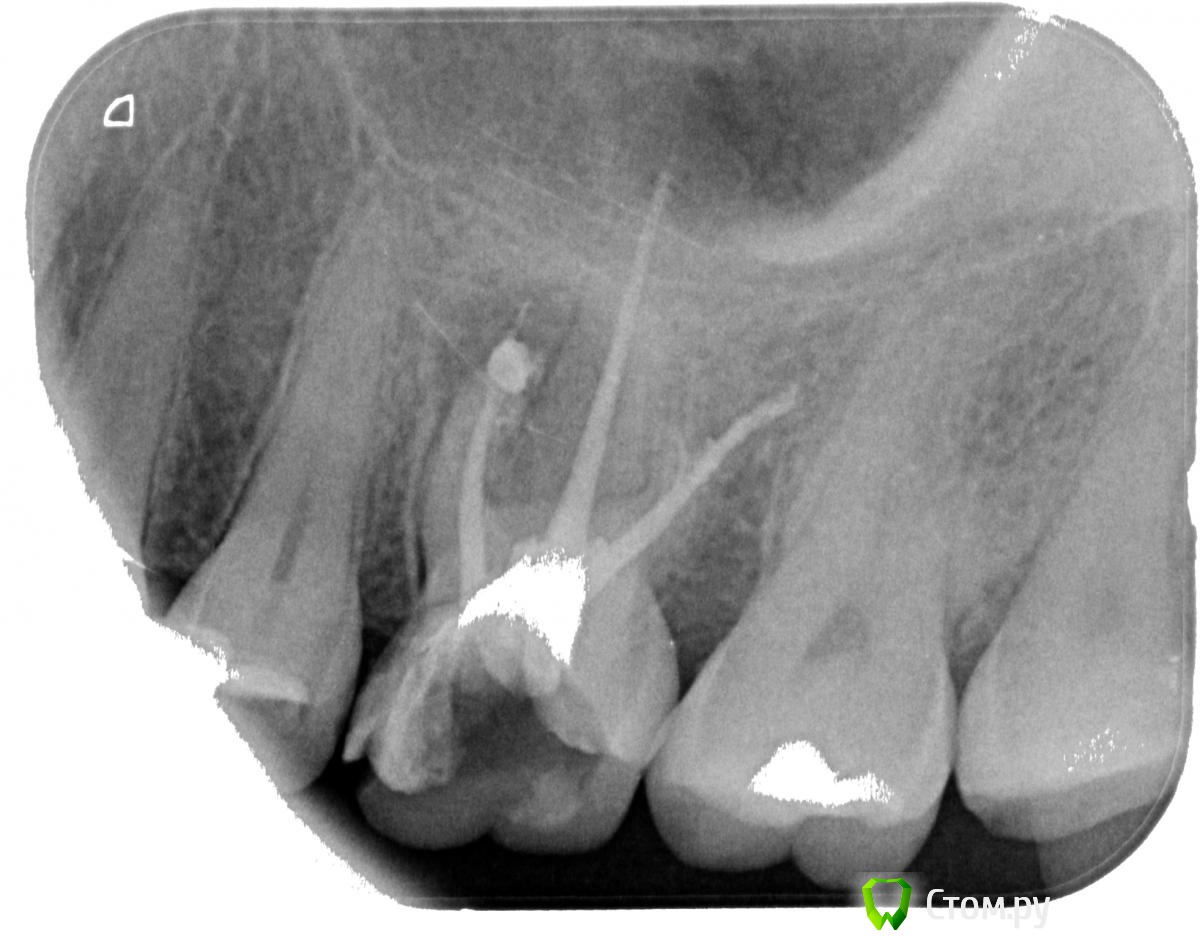

oksanab Опубликовано 2 октября, 2014 Поделиться Опубликовано 2 октября, 2014 (изменено) Консультировалась уже с 4-мя ортопедами, при чем кандидатами мед. наук, и они как-то расходятся во мнении. История такая: 12 лет назад зуб депульпировали, лет через 6 я стала ощущать дискомфорт, и на снимке было воспаление. (снимок 1). А теперь 1,5 месяца назад воспалились немного десна и через какое-то время появился флюс. Вскрыть десну я побоялась и пропила антибиотики. Флюс сошел, но десна еще оставалась припухлой слегка. Я после этого, то есть после антибиотиков, пришла к ортопеду, он начал лечить каналы 26-го зуба, и дискомфорт в десне на половину уменьшился, то есть явно стало получше. В этом зубе так же был обнаружен кариес, но врач сказал, что после лечения каналов удалит кариес, может за стенки боялся). Но во время лечения, когда стояла лечебная паста, на отдыхе зуб сломался об косточку оливки(стояла временная пломба с пастой лечебной). Ортопед через 20 дней убрал лекарство и запломбировал каналы эндометазоном(про гутаперч ничего в выписке не пишет, только это). Когда пломбировал, просил у медсестры что-то 40-е или хотя бы 38-е, у них не оказалось(может штифты...). Уж не знаю чем они там обошлись, но меня такая клиника напрягла. Врач поставил временную пломбу, удалил кстати, отломавшийся кусочек зуба, и сказал приходить через 3 дня, чтобы удалить кариес в этом зубе и смотреть его устойчивость, чтобы определиться с коронкой или вкладкой. Поскольку в этой клинике вечно чего то нет, я перешла в другую. Пришла к кандидату мед. н аук с 25 летним стажем. Он заявил, что скорее всего нужна резекция корня зуба, и отправил меня в институт научно-исследовательский(ЦНИИС и ЧЛХ). Так я попала к следующему к.м.н.- ортопеду Мурадову. Этот радостно сообщил ,что все замечательно, резекции не надо. Но он пропустил кстати перфорацию корня у дистально щечного канала , как и первый к.м.н., он тоже пропустил ее,( его только воспаление у десны обеспокоило, поэтому отправил в институт на консультацию в институт.) А вот уже в институте второго ортопеда -к.м.н. -Мурадова, ничего по десне не обеспокоило, сказал будем ставить коронку. Пока ждала 2 недели очередь , так уж получилось, что я сходила еще к одному ортопеду, чтобы заменил временную пломбу. Он посмотрел снимок, и он первый из врачей, кто вообще заявил, что есть перфорация корня и зуб надо удалять! Однако, я вернулась все таки пошла на лечение к Мурадову ,который радостно брался за этот 26 зуб. И когда я пришла на лечение через 2 недели по его огромной записи, тут вдруг выяснилось... Он вскрыл зуб, сказал что-то про запах, сразу его запаял и заявил, что паста мягкая, надо перепломбировать. Паста - эндометазон. Я попросила повнимательнее посмотреть на снимок, и посмотреть есть ли там перфорация. Тут наконец-то перфорацию заметил и он, хотя видел снимок и две недели назад, и сегодня перед началом лечения. В итоге мне заявил, что, ну пусть терапевт разберется есть там перфорация или нет, потому что на обзорном снимке видно, что угол у зуба другой. Прилагаю три снимка(зуб до лечения, и общий снимок до лечения, и зуб после лечения и пломбировки каналов эндометазоном и уже со сколом зуба). Так вот он все-таки не совсем понял, есть ли перфорация канала. Отправилась я тогда к зам. главного врача этого института ,она оказалась тоже к.м.н. и именно ортопед. Может она конечно хотела прикрыть Мурадова, не знаю, но сказала, что хотя она не очень знает эндометазон, но тоже считает, что надо сделать перепломбировку. На мой вопрос почему врачи, да еще и к.м.н. не замечают перфорацию, ответила, что это конечно не хорошо, но и ей лично кажется, что все-таки перфорация есть. Однако ей было сложно рассмотреть мои снимки на айфоне, то есть я показывала снимки с своего телефона. Поэтому она порекомендовала мне записаться к их терапевту, чтобы внимательнее просмотрел все, может снимок сделал еще один, и чтобы перепломбировали канал методом латеральной конденсации, и пролечили перфорацию. И кстати говоря ,не рекомендовала не резекцию корня зуба, ни его удаление. По факту что у меня получается. Первый к.м.н. - за резекцию корня. Остальные три против резекции. Пятый ортопед вообще за удаление. И вот через 4-5 дней из-за очередей попаду к их терапевту какому-то толковому, тоже будет мозговать, есть ли перфорация, и чего делать то. Народ спасите. ЁПРСТ, я с этим зубом уже полтора месяца хожу, а они только трепятся, а за лечение никто еще не взялся. Только мне все истории разные рассказывают. Я уже готова и удалить его, хотя очень импланта боюсь. И готова рискнуть, поставить коронку, а если чего будет, ну резекцию тогда. Но тот врач, который сказал, что зуб надо удалять, сказал, что и резекция всего лишь временно поможет и толку в ней не будет. Блин, блин, блин... Как я простой человек могу в этом разобраться. И вообще , я больше месяца только на одну сторону жую ,это же тоже наверно не очень хорошо. Перелеченный недавно зуб на втором снимке со сколом зуба. Изменено 2 октября, 2014 пользователем oksanab Ссылка на комментарий

Cleric Опубликовано 3 октября, 2014 Поделиться Опубликовано 3 октября, 2014 (изменено) Во-первых, эндометазоном и прочими пастами уже давно не пломбируют каналы, т.к. они показывают плохие результаты в виду отстутствия герметизма, а также наличия гормонов в составе (каналы должны пломбироваться гуттаперчей на эпоксидном силере)Во-вторых, воспаление наиболее вероятно возникло из-за пропущенного 4го канала, т.е. в переднем щечном корне не 1 канал, а 2.В-третьих, многое зависит от глубины скола стенки, если глубоко под десну - то шансов на адекватную реставрацию немного.Вам необходимо найти врача стоматолога-эндодонтиста и спасти зуб от удаления и прочих к.м.нов с институтах В Москве есть много прекрасных специалистов по эндодонтии, но лечение стоит немалых денег, но оно СТОИТ того. Изменено 3 октября, 2014 пользователем Cleric 1 Ссылка на комментарий